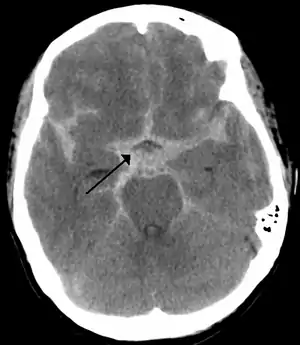

| یک سی تی اسکن از خونریزی زیر عنکبوتیه که در آن به صورت ناحیه سفید رنگ در مرکز که به سمت سولکوسهای در طرفین گسترده شده مشاهده میشود. | |

تشخیص با استفاده از سی تی اسکن بدون استفاده از ماده کنتراست صورت میگیرد. در مواردی ممکن است از کشیدن آب نخاع (LP) برای تشخیص استفاده شود. همچنین از روشهای تشخیص دیگر همچون امآرآنژیو، سیتیآنژیو، میتوان استفاده کرد. استاندار طلایی تشخیصی برای آنوریسمهای مغزی آنژیوگرافی عروق مغزی است.